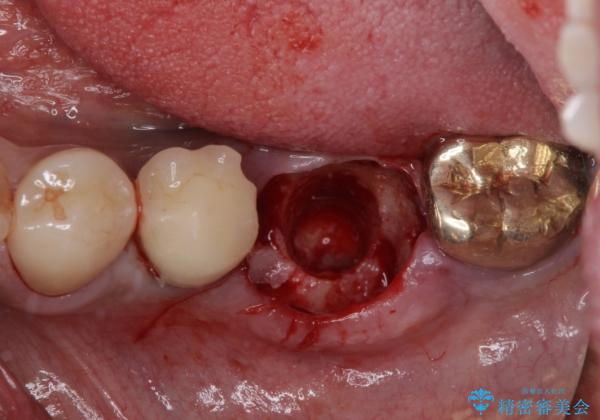

そのため、当院に新しく導入した手法により、抜歯をした日にインプラントを埋入し、そのままを仮歯を装着することで、他の歯への負担を軽減する計画を立てました。

インプラント埋入時に植立具合の安定性を測定したところ、十分な数値が得られたため、速やかに仮歯を装着して咬合回復をさせることができました。

抜歯を含めた外科処置を1回に抑えることができ、あっという間に治療を終えることができました。